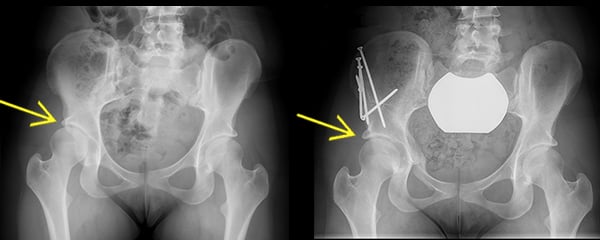

Anterior to posterior X-ray images, before and after a PAO. Left X-ray shows dysplasia of the right hip; the acetabulum is underdeveloped and provides incomplete coverage of the femoral head. Right X-ray shows complete healing of a periacetabular osteotomy, with improved coverage of the femoral head by the acetabulum.

In a periacetabular osteotomy, the surgeon makes a series of cuts to the bone to reposition the acetabulum in the pelvis, in order to restore a more normal hip joint anatomy. Screws are then placed in the bones to stabilize this position. During the healing process, new bone forms across the cut surfaces to secure the repositioned acetabulum in the pelvis, establishing proper alignment of the hip joint ball and socket.